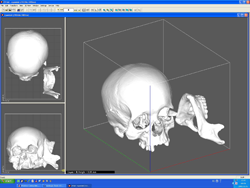

A koponya CT felvételéből készült 3D rekonstrukció |

|

Ezt követően 3D nyomtató készülékkel ”kinyomtattuk” annak műanyag térbeli másolatát, amelyre elkészítettük az arcrekonstrukciót.